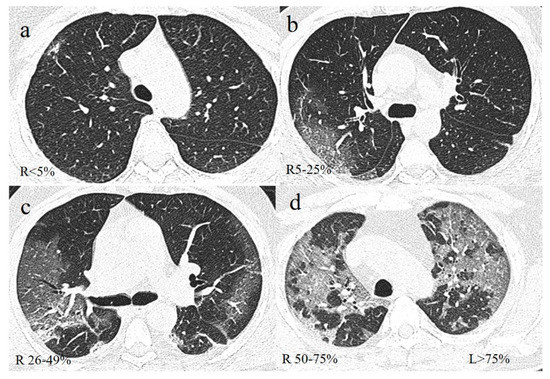

| Guillo et al. [108] | 214 patients | Severity of COVID-19 pneumonia graded as minimal (<10% lung parenchyma), moderate (10–25%), intermediate (25–50%), severe (50–75%), critical (50–75%). | 68 % of patients with disease extent exceeding 25 % of the lung parenchyma were intubated or deceased in the 3 weeks following CT. |

| Wang et al. [149] | 161 patients | CT visual severity levels:

| Higher CT-SS were associated to the severity clinical course. Non-survivors showed much higher CT-SS compared with survivors, without a visually apparent decrease between week 1 and week 2. |